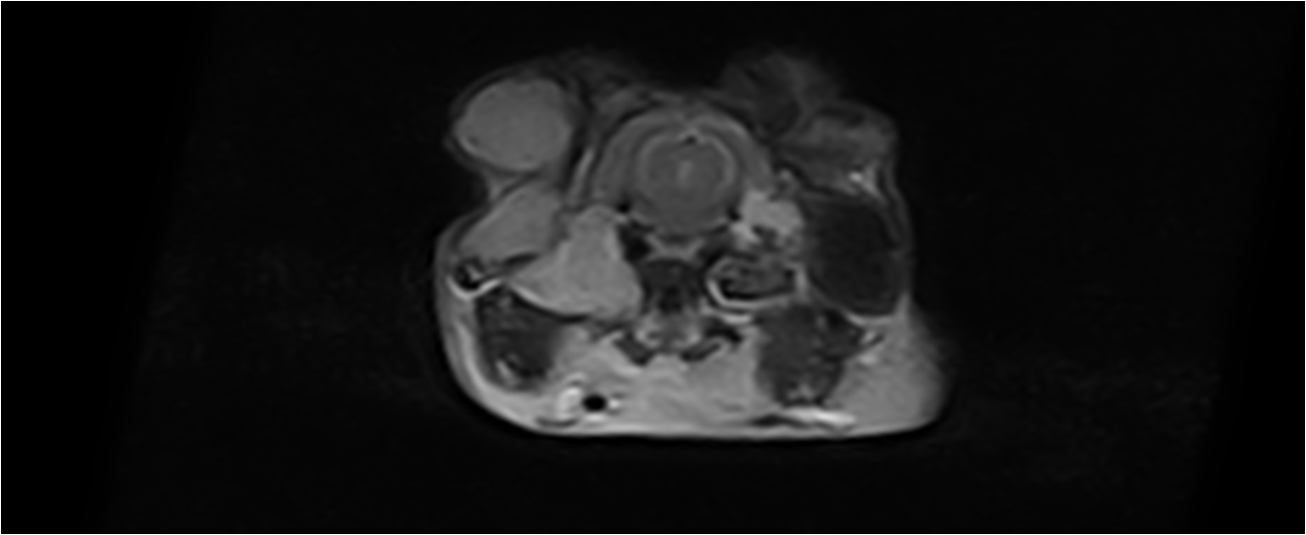

On distingue les otites externes qui affectent le pavillon auriculaire externe, les otites moyennes qui concernent la partie osseuse de l'oreille (bulle tympanique) et qui se situe sous le tympan (donc non visible extérieurement) et les otites internes (organe de l'équilibre). L'observation se fait préférentiellement par endoscopie ou otoscopie. Le diagnostic d'otite moyenne se fait à l'aide d'un scanner ou un IRM préférentiellement. En fonction de l'atteinte considérée, plusieurs techniques chirurgicales peuvent être recommandées pour permettre la vidange des bulles tympaniques (bullotomie ventrale, PECALBO ou chirurgie d'abaissement du conduit auriculaire). Des techniques endoscopiques sont également possible pour aborder la bulle tympanique (myringotomie).

Les otites provoquent généralement des démangeaisons et parfois des syndromes vestibulaires avec un torticolis (tête penchée) et des crises convulsives.

Les otites sont fréquentes chez les lapins en particulier chez les lapins de race bélier mais aussi chez les cobayes et les rats.